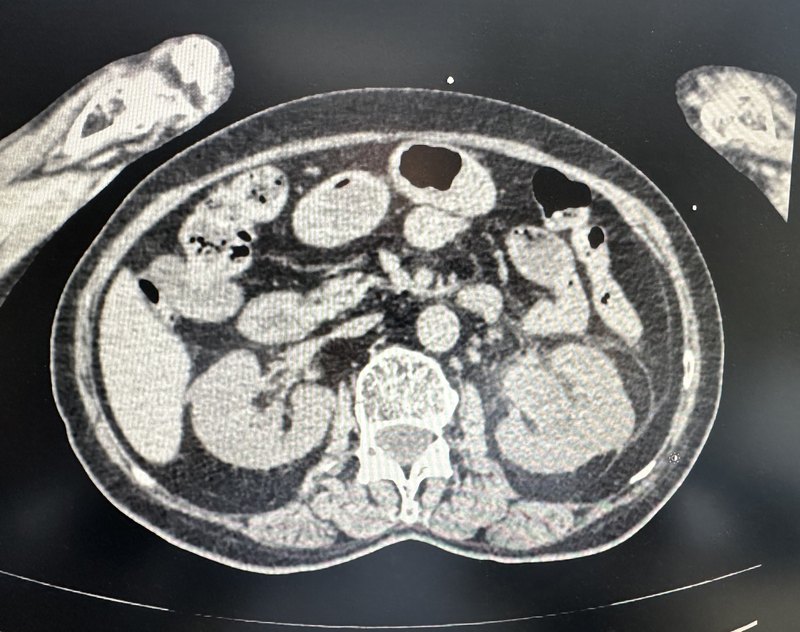

近日,收治了一名女性患者,主因“左腰部疼痛1天”入院。入院查血常规,血象,中性粒细胞升高,提示感染。查肾功能示:血肌酐升高为393umol/L,肾小球滤过率降低至12.3。患者泌尿系CT显示左肾积水严重,一枚大结石堵在输尿管里,右肾多发结石。考虑患者结石引起严重积水并有感染征象,高度怀疑肾积脓可能。故急诊行B超引导下经皮左肾穿刺造瘘术。术中情况:术前检查的肌酐和肾小球滤过率和术后的对比:明显改善术前,术后CT对比,积水明显减轻;左肾造瘘位置良好。患者目前恢复良好,待II期行经皮肾镜碎石取石术。温馨提示:肾内大结石早期往往没有任何症状,一旦出现感染或充满集合系统就会带来严重的后果,即肾积脓,肾功能严重受损。所以患有肾结石的患者一定要早发现,早处理,避免严重并发症的出现而后悔莫及。